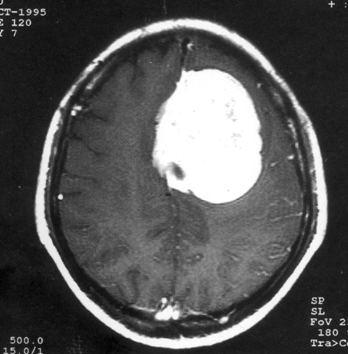

问题 病历摘要:??患者女性,37岁。大便时突起炸裂样头痛3小时,伴喷射样呕吐。既往体健。体检:T37.5℃,BP145/90mmHg,R20次/分,P85次/分。神志清楚,颅神经检查无异常,颈强直,克、布氏征(-),四肢肌力、肌张力正常,病理征(-)。 应首先采取哪些处理措施?提示:CT示右额叶直回处小血肿、蛛网膜下腔出血。